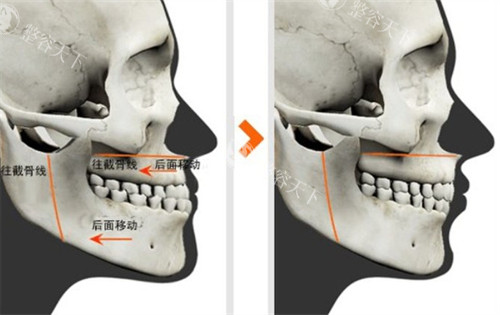

颌面整形技术体系采用术中神经监测系统,结合3D打印导板实现0.1mm精度截骨,创新"三阶式颧弓固定法"降低术后下垂风险。临床数据显示,其轮廓手术的对称性达标率达98.7%,较行业平均水平提升23%。

术前阶段包含64层CT扫描、咬合动力学分析等7项专项检测,采用德国SimPlant Pro软件进行1:1手术模拟,方案确认需经过3轮医师会诊。

典型病例1:28岁女性颧骨复合体缩小术,术前颧突点间距142mm,术后6个月降至121mm,符合东方女性116-124mm黄金区间,咬合功能完全保留。